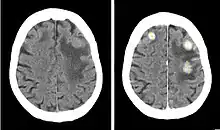

CT scan of three brain metastases from breast cancer. Before (left image) and after (right image) injection of an iodinated contrast agent similar to iobitridol.

Iobitridol is an iodine-containing radiocontrast agent.[2][5] The iodine atoms readily absorb X-rays, resulting in better contrast in radiography images.[9] The quality of images made with this drug is equally good as with other low– or medium–osmolarity iodinated contrast agents such as iopamidol or iohexol.[5]